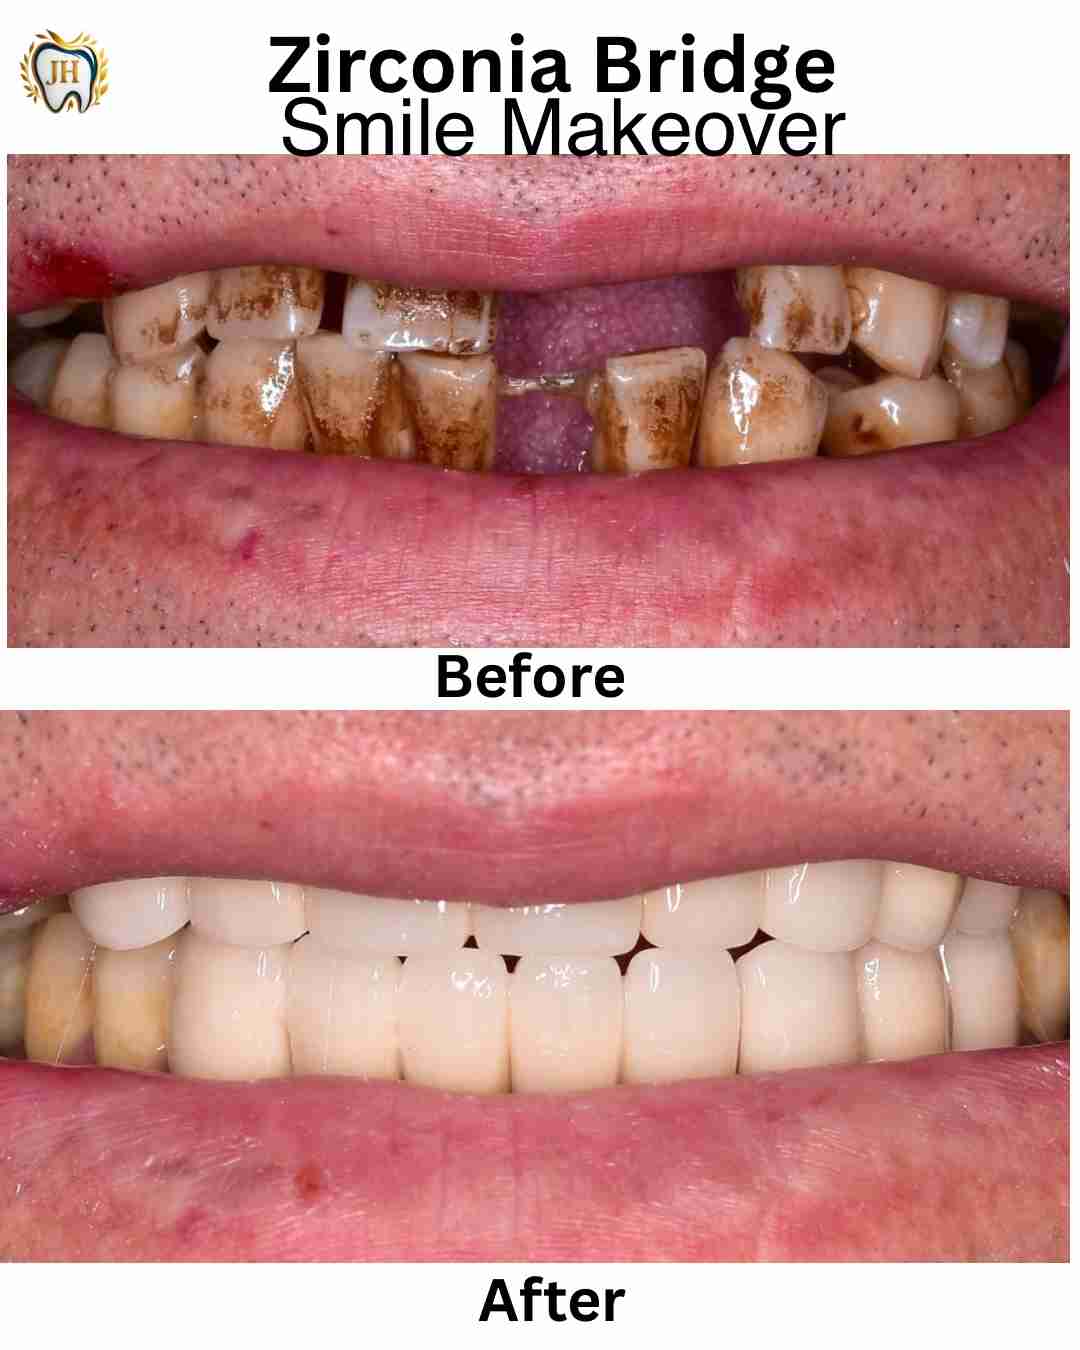

- Smile Makeovers

- Crowns & Bridges

- Transformations